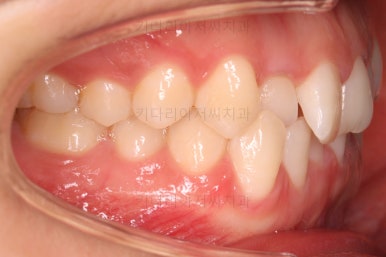

웃을 때 장치 부착 직후의 옆모습을 보시면 장치 부착에 따른 얼굴 변화 모습을 대략 아실 수 있을거에요.

점점 가지런해지고 있네요.

옆라인이라던지 입을 다물었을 때의 느낌은 원래도 좋으셨기 때문에 거의 그대로 유지가 되었고요.